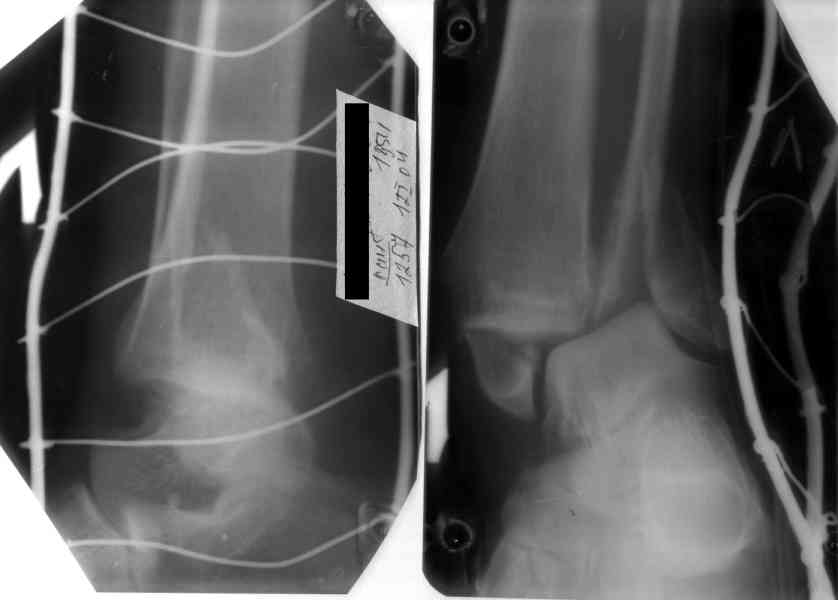

На 4-й неделе убрал спицы, с 7-й недели начал ЛФК, дозированную нагрузку, физиопроцедуры, массаж. Назначил хондропротекторы. Получилось вот что.

Rg-05.JPG

Удалены спицы, а гипса не было? 3-х лодыжечный перелом фиксировать 4 недели недостаточно. Что и подтверждается на последнем снимке - есть тенденция к подвывиху кнаружи, кзади... Что будет дальше, когда пациент начнет давать полную нагрузку?

Малоберцовая выглядит коротковатой. Профиль как-то мутный. Вообще, неплохо было бы сделать снимки в сравнении со здоровой.